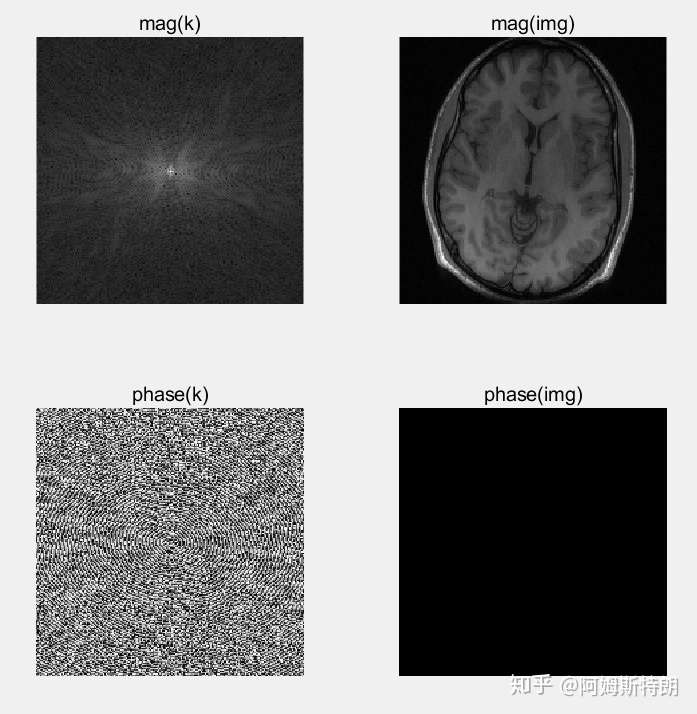

一句话,k空间中的幅度决定强度信息,相位决定位置位置信息。

而k空间中储存的是一个复数,其幅度代表平面波的波动的大小,相位代表平面波的相位也就是偏离原点的多少。

而最终,从k空间恢复图像的时候,是将每个复平面波乘上对应的复系数,相加而成。可以分为两步:1、乘波动大小(幅度)2、移动相应的距离(相位)。

- 若一个图像是实数图像,那么k空间是关于中心复共轭的。复共轭是为了使得复平面波相加的时候将虚部都互相抵消掉,只留下实部,然后所得图像就是实数图像。

- 如果使得k空间的phase全部等于0,那么相当于平面波在相加的时候,都没有移动,所以图像一定会呈现一种周期性,而且中间的点一点很亮。这是因为复平面波没有移动,那么所有的平面波在中心点相位为0,exp(0)=1,因此相当于所有的幅度叠加在一起了。如下图:

- 如果使得k空间的magnitude全部等于1,那么相当于平面波在相加的时候,只有移动,而没有了各个波的大小信息,低频成分和高频成分全都一样了,所以图像应该比较嘈杂,变化比较剧烈,但是能看见大体的轮廓,如下图: